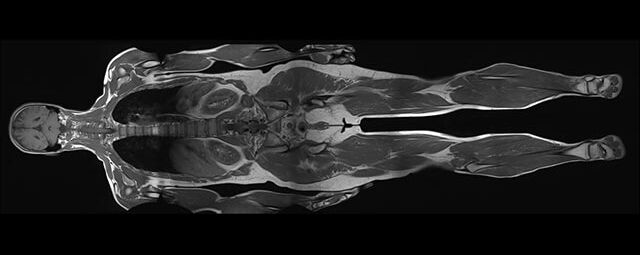

Im Magnetresonanztomographen liegt die zu untersuchende Person in einem starken, homogenen Magnetfeld. Dieses Magnetfeld bewirkt eine gemeinsame Ausrichtung der Wasserstoffprotonen im Körper entlang der Längsachse des Magnetfeldes. Wird nun diesen Teilchen Energie in Form von Radiowellen in einer genau abgegrenzten Frequenz zugeführt, so werden sie aus ihrer ursprünglichen Orientierung abgelenkt.

Die zugeführte Energie wird in gewebespezifischer Weise wieder abgegeben. Ein hochempfindliches Computersystem misst die unterschiedliche Energieabgabe und setzt sie in Bildinformationen um. Jede Körperregion kann somit durch Schnittbilder in allen Raumebenen oder durch dreidimensionale Rekonstruktionen mit einem exzellenten Weichteilkontrast dargestellt werden. Es besteht keine Belastung durch Röntgenstrahlen.

Die MRT wird immer dann eingesetzt, wenn Verfahren mit Röntgen oder Ultraschall keine klaren Aussagen liefern können oder wenn dynamische Prozesse des Körpers untersucht werden sollen.

Die Aussagefähigkeit der MRT ist bei den folgenden Fragestellungen besonders geeignet. Zur Einschätzung der Wertigkeit der MRT gegenüber anderen bildgebenden Verfahren, wie Computertomographie, Sonographie oder Röntgen stehen Ihnen unsere radiologischen Fachärzte zur Verfügung.